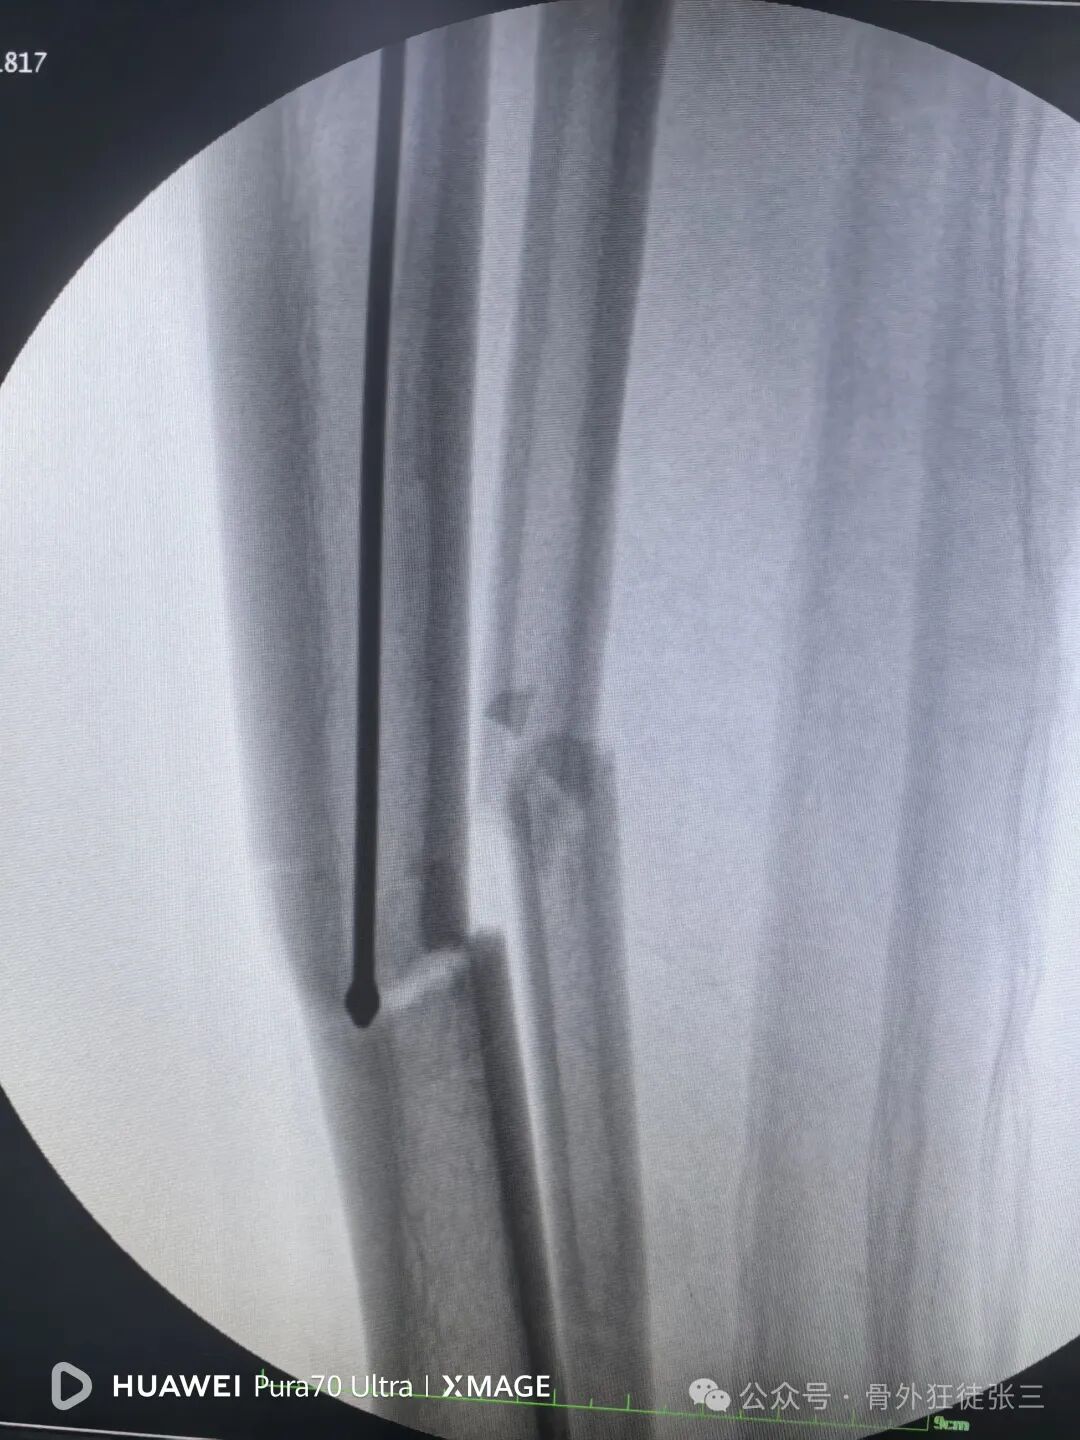

远端安装瞄准架

骨折间隙顺利缩小